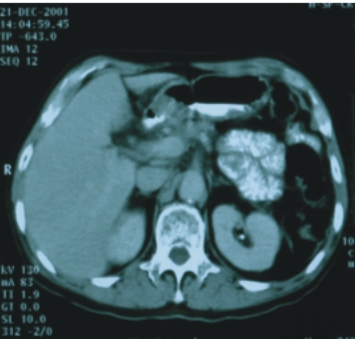

56歲/男性 (肝癌合併後腹腔淋巴腺轉移) |

74歲/男性 (直腸癌合併後腹腔淋巴腺轉移) |

||

| 90/5/2

(治療前) |

90/6/30(治療後) |

90/8/16(治療前) |

90/12/21(治療後) |